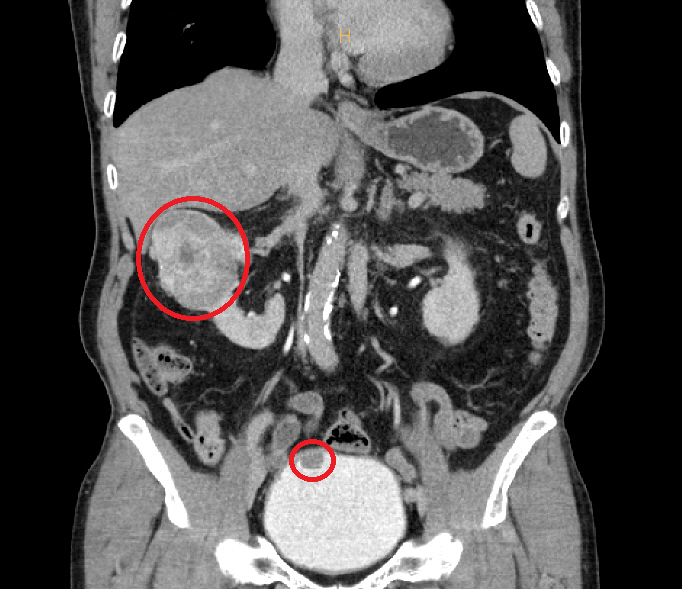

Kim (73, male), who underwent surgery this time, found bladder cancer in his bladder along with renal cell cancer measuring about 7cm in one kidney. Professor Lee Sang-wook performed a robotic kidney partial resection using the Da Vinci Xi robotic surgery machine to precisely resect tumors by enlarging the surgical site up to 15 times to a 3D screen. Partial renal resection is a high-level surgery that requires temporary ligation of the renal artery to reduce bleeding. Bladder cancer was removed by transurethral resection using an endoscope.

Professor Lee Sang-wook chose partial resection because he thought protecting the kidney function was very important to the patient's quality of life, although both cancers were found at the same time in the patient and the size of the kidney tumor was large"Sunchon Hyang University Bucheon Hospital performs customized surgery for patients based on various high-level robotic surgery experiences to produce optimal treatment results."